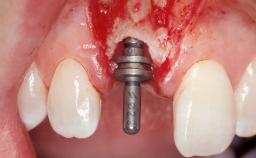

Immediate Flapless Placement of an Implant in a Maxillary Left Central Incisor Site

A 29-year-old female patient presented for treatment to replace the upper left central incisor tooth with an implant- supported restoration. The tooth had been intermittently symptomatic for the previous 12 months. The tooth had originally suffered trauma about 15 years previously. Several endodontic treatments had been performed, including an apicectomy procedure to retain the tooth. The patient was healthy and a non-smoker. She had reasonable expectations in regard to esthetic outcomes and the risk of marginal tissue recession following treatment. At medium smile, the gingival margins of the upper teeth were visible, with a display of 3 to 4 mm of the gingival margins. Gingival recession of tooth 21 and a discrepancy in the gingival levels between teeth 11 and 21 was observable during normal speech and smile.

Placement Protocol Immediate implant placement

Tooth Site Maxillary incisor or canine

Socket Morphology Single-root socket

Socket Integrity Damage to one or more bone walls

Bone Volume Damage to one or more socket walls